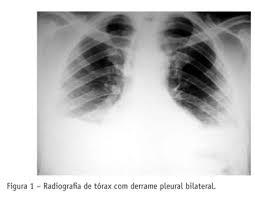

2. Imagenología

1. Desplazamiento hacia afuera del vértice del diafragma

1. con una pendiente súbita hacia el surco CF

1. Separación > 2cm entre la búrbuja de aire gástrica y pulmón

2. RX

1. Lateral

1. 75-100 mL acúmulo en surco costofrénico- POST-> visible

2. PA

1. 175-200 ml surco CF Lateral --> deliniarse imagen frontal